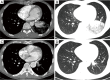

Results: Twenty-eight patients, 15 male and 13 female, with a median age of 42.5 underwent operative intervention for PS. Twenty-one patients showed preoperative symptoms including cough, expectoration, hemoptysis, chest and/or back pain, and fever. General chest computed tomography (CT) scanning; percutaneous needle biopsy, bronchoscopy, enhanced CT scanning, and CT angiography (CTA) were used as diagnostic methods. Twenty-one patients were diagnosed preoperatively by enhanced CT scanning and CTA; seven patients were confirmed by surgery. Twenty-one patients underwent surgery (15 cases via thoracotomy and 6 cases via video-assisted thoracic surgery), seven patients underwent interventional therapy (three cases via endovascular embolization and four cases via thoracic aortic endovascular stent-graft exclusion). Three patients had a complication in surgery group (intraoperative hemorrhage in two patients and postoperative hydropneumothorax in one patient) and two patients had post-embolization syndrome in interventional group (fever and pain at embolism site). During the follow-up period ranging from 6 to 84 months, no recurrences or further complications were observed in two groups.

Conclusions: Enhanced CT or CTA may be a potential approach for the diagnosis of PS. Surgical resection for PS is the major treatment approach. Endovascular embolization of PS could be considered when pulmonary lesion is small-sized. Endovascular exclusion could be used to treat combined arterial aneurysm and dissection of PS.